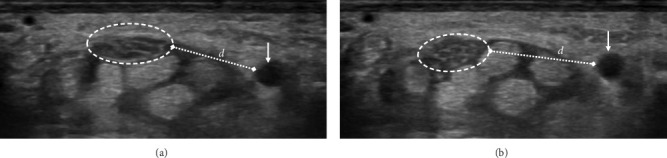

目的:本研究旨在评估各种超声标准对腕管综合征(CTS)严重程度分级的价值。方法:由经验丰富的放射科医生对确诊的CTS患者进行超声评估,对NCS结果不知情。测量旋前方肌横截面积(CSA)、腕管进出口、回声性、屈曲时的横向运动、压平率和屈肌支持带增厚。结果:正中神经回声减弱是轻度和中度病例的显著特征。神经运动减少在严重的CTS病例中更为普遍。两组正中神经压平率和屈肌视黄带厚度无显著差异。进气道弯曲有显著性差异。进口和出口的CSA显示严重的CTS,差异有统计学意义。结论:虽然正中神经压平率和屈肌视黄带厚度无明显差异,但超声多指标对准确诊断和治疗具有重要意义。

Objective: This study aimed at assessing the value of a variety of ultrasound criteria for grading carpal tunnel syndrome (CTS) severity. Methods: Ultrasound evaluations were conducted on confirmed CTS patients by an experienced radiologist, blinded to NCS results. Cross-sectional area (CSA) at pronator quadratus muscle, carpal tunnel inlet and outlet, echogenicity, transverse motion during flexion, flattening ratio, and thickening of the flexor retinaculum were measured. Results: Decreased echogenicity of the median nerve was notably observed as a distinguishing feature between mild and moderate cases. Decreased nerve movement was significantly more prevalent in severe CTS cases. No significant differences were found in the median nerve flattening ratio or flexor retinaculum thickness. Bowing at the inlet showed significant differences. CSA at the inlet and outlet indicated severe CTS with significant differences. Conclusion: The findings highlight the importance of using multiple sonographic criteria for accurate diagnosis and treatment, although no significant differences were noted in the median nerve flattening ratio and flexor retinaculum thickness.